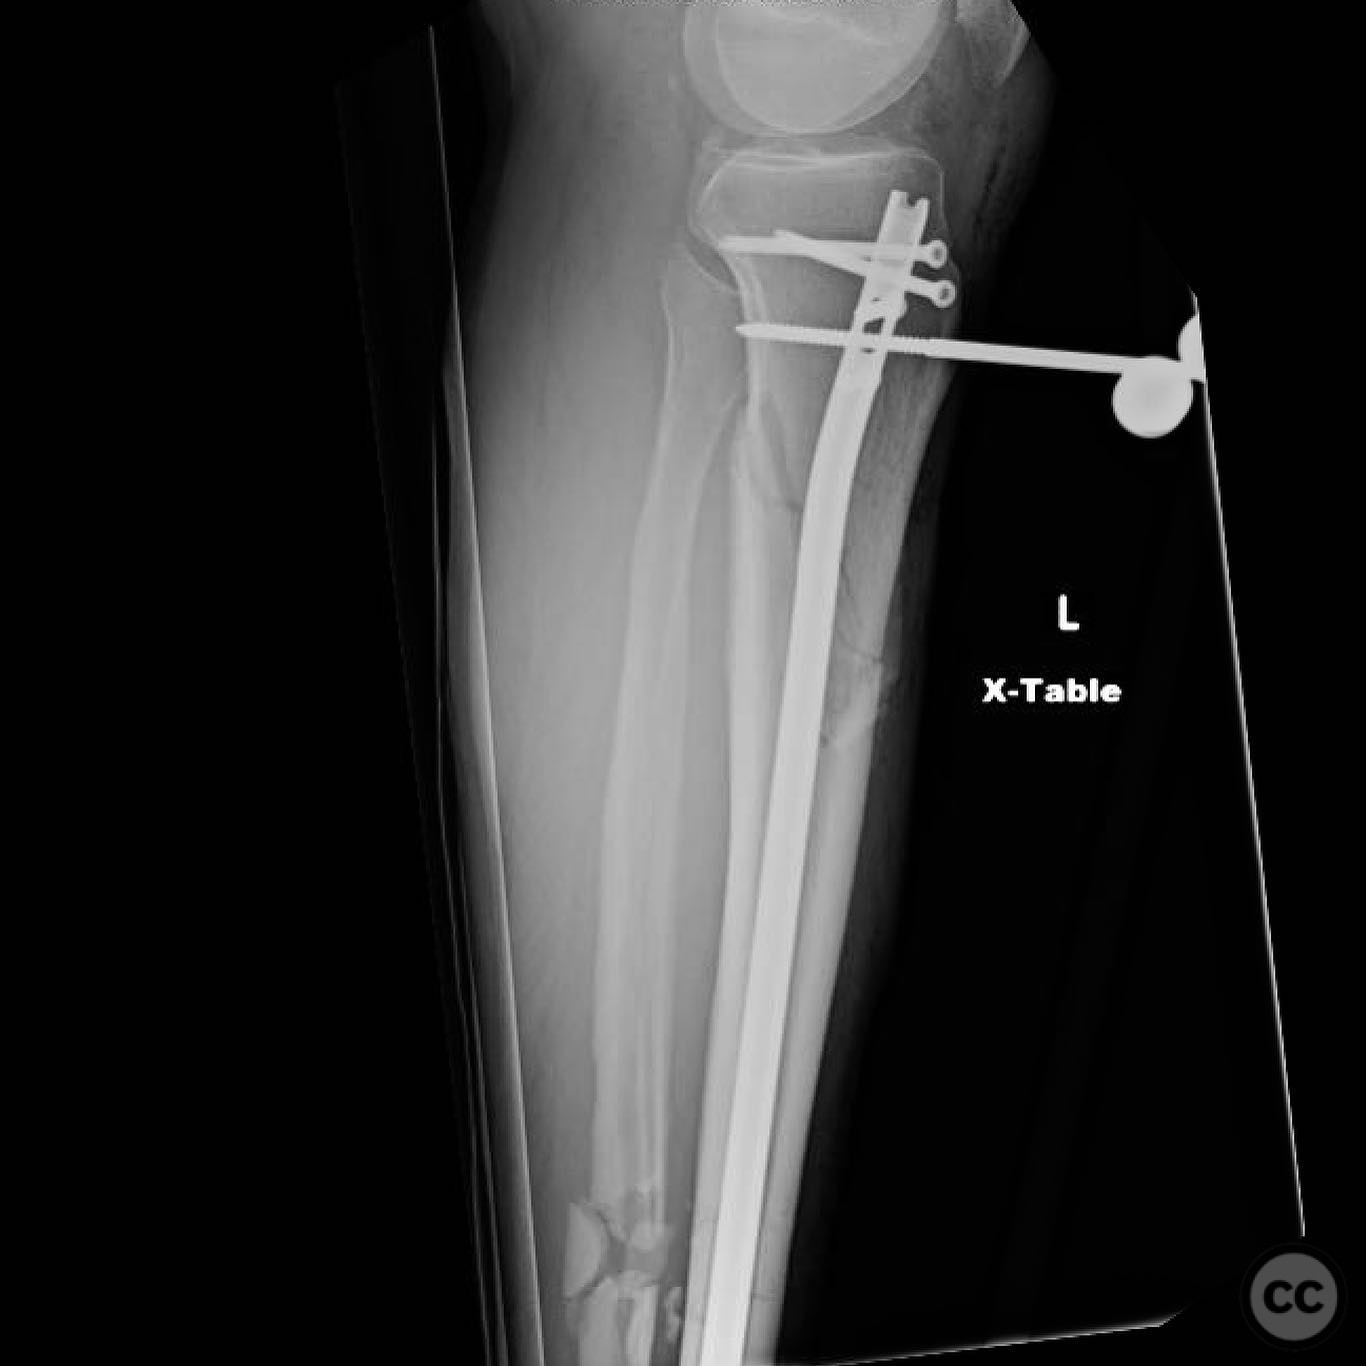

Anatomical surgical approach:  For the tibia, a longitudinal incision was made to access the proximal tibial start site for intramedullary nailing. Percutaneous clamps were utilized for reduction, supplemented by blocking screws as needed. For the distal femur, an external fixator was applied initially, followed by an in situ lateral approach for plating after reduction was achieved.

The tibial nailing required precise identification of the start site under fluoroscopic guidance, with percutaneous clamps aiding in reduction. Blocking screws were considered but not necessary due to successful reduction with clamps alone. The distal femur presented challenges in achieving coronal and sagittal alignment, necessitating reliance on the external fixator for reduction before proceeding with plating.

Orthopaedic implants used:   Intramedullary nail for tibia, external fixator for initial femoral stabilization, and locking plate for definitive femoral fixation.